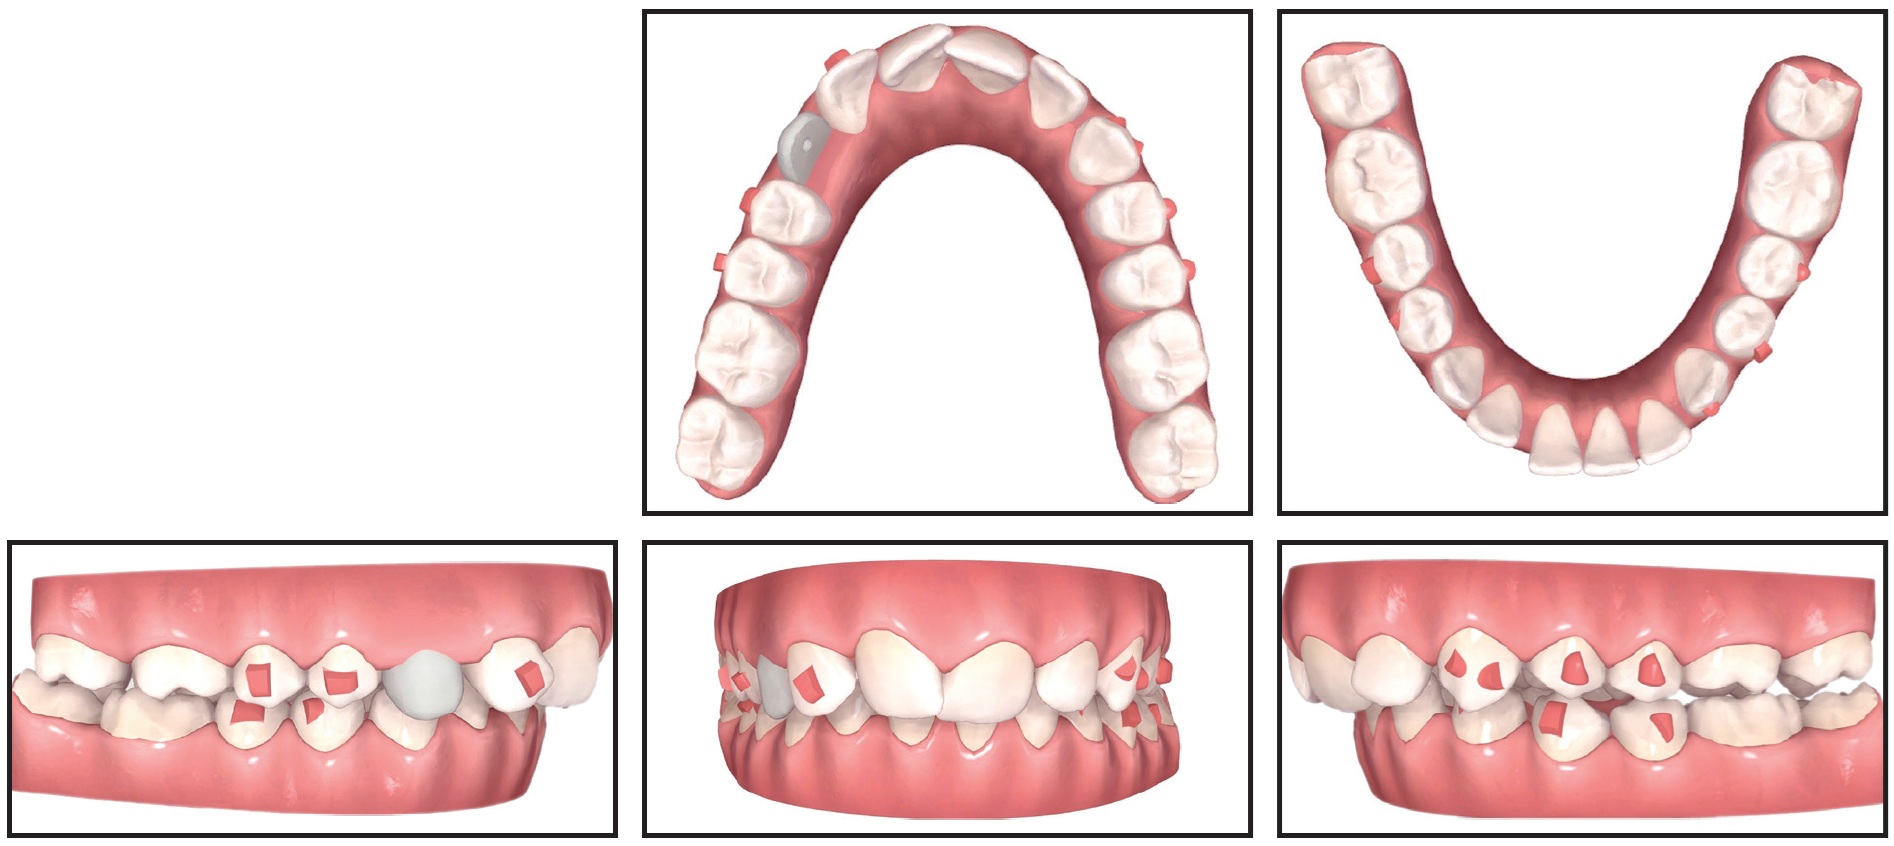

Clear Vivera* overlay retainers were delivered to be worn at night in both arches. The results remained stable one year after treatment (Fig. 8).

Fig. 8 Patient one year after treatment.